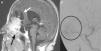

Case reportOur patient was a 65-year old female with anosmia and cognitive deterioration. Cranial MRI showed a large tumoral lesion with solid and cystic components involving the nasal cavity, with diagnostic suspicion of intracranial malignant sinonasal tumour. The patient underwent a fully endoscopic transcribiform-transfovea ethmoidalis EEA, achieving total resection and tumour-free margins. Surgery was followed by radiotherapy.